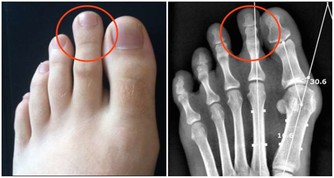

②惡性腫瘤淋巴結轉移,已經出現癌細胞轉移的淋巴結,質地比較硬,表面會有凹凸不平的樣子,還會和皮膚發生粘連,一般沒有疼痛感;

③淋巴結結核,當淋巴結內部出現壞死時,破爛潰瘍後就會形成瘻管。